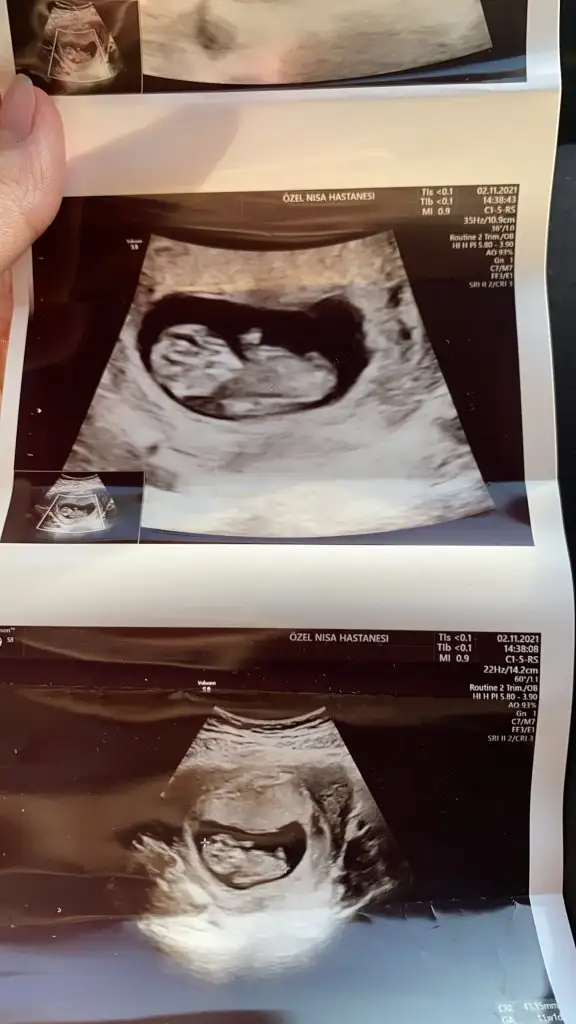

Suan kac haftalik acaba? Tam belli olmuyor malesef

11Suan kac haftalik acaba? Tam belli olmuyor malesef